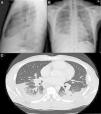

A) Radiografía de tórax PA. B) Radiografía de tórax lateral, se observan infiltrados alveolares parcheados en LM y LSI. Derrame pleural bilateral de predominio derecho. Adenopatías hiliares y mediastínicas en rango patológico. C) Imagen axial de la TC torácica con CIV, se observa el componente adenopático en compartimentos mediastínicos, hiliares bilaterales y periesofágico. Afectación alveolar bilateral de predominio subpleural bibasal con lesiones nodulares hacinares y broncograma aéreo de distribución subpleural parcheada.

Varón de 38 años, natural de Ghana. Diagnosticado en 2003 de tuberculosis (TB) latente, sin realizar quimioprofilaxis y episodios de malaria durante la infancia. Consulta por tos con expectoración hemoptoica, disnea, dolor torácico pleurítico de 2 meses de evolución acompañado de pérdida ponderal, sin fiebre. En la exploración física destacaba hipofonesis en base derecha con crepitantes y roncus hasta campos medios bilaterales. En la radiografía de tórax se objetivaban múltiples infiltrados alveolares basales bilaterales con hilios de aspecto nodular que sugerían la presencia de adenopatías acompañado de DP derecho (figs. 1A y B). Analíticamente destaca, LDH de 134 con disminución de las proteínas y albúmina, PCR de 63mg/dl y VSG de 47. Espectro electroforético de proteínas con patrón inflamatorio sin pico monoclonal, con autoinmunidad negativa y serología para VIH y VHC negativo, con VHB y VHA pasada. ECA de 89,2 (normalidad<50). Mantoux con efecto booster negativo. En la toracocentesis se obtiene líquido seroso compatible con exudado de predominio linfocitario, ADA de 72. Las tinciones, cultivos, y técnicas moleculares específicas de micobacterias y hongos resultaron negativas; inmunofenotipo sin datos de clonalidad, mostraba importante población linfoide T con una relación CD4+/CD8+ de 4/1 (>3,5). Tras el PET/TAC tóraco-abdominal (fig. 1C) se realiza broncoscopia con biopsia transbronquial, objetivándose granulomas epitelioides necrotizantes no caseificantes. Diagnóstico final de sarcoidosis pulmonar estadio II con DP secundario.